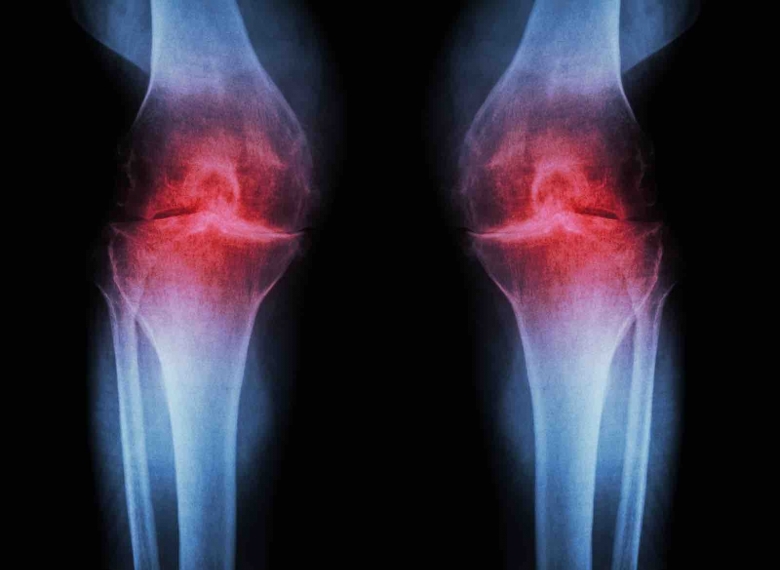

La problematica del ginocchio valgo è assimilabile ad una lenta deformazione del ginocchio che tende quindi verso l'interno. Questo accade in particolare quando il femore e la tibia non risultano essere allineati e quindi finiscono con il formare una sorta di angolo ottuso, più comunemente conosciuto come “ginocchia a x”.